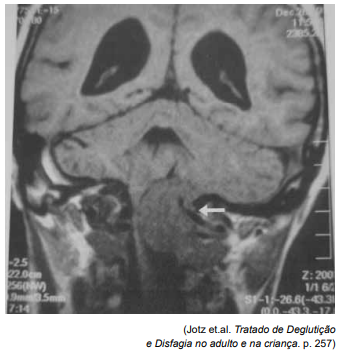

Observe a imagem em corte coronal feita por Ressonância Magnética de crânio, na fase sem contraste.

Assinale a alternativa que apresenta a avaliação correta da região apontada pela seta branca.